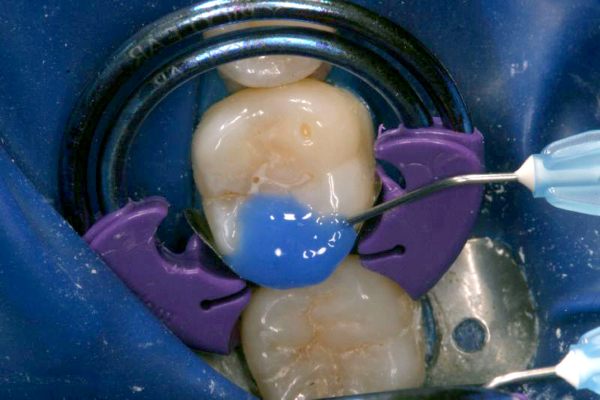

Click on an image below to enlarge & view caption.

Dentistry and photography courtesy of Dr. Robert Margeas.